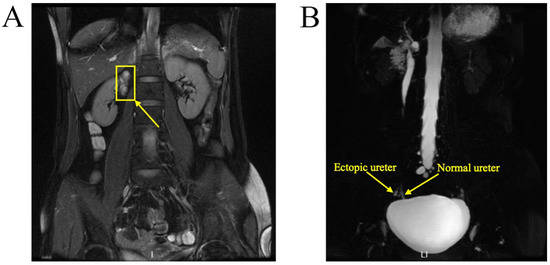

A 37-year-old woman was referred to our hospital for persistent vaginal discharge. After she underwent vaginal cyst excision 11 years ago, she began to experience persistent vaginal discharge, requiring two sanitary pads daily. A pelvic examination revealed a pinpoint-like hole in the right anterior wall of the vaginal fornix. It was observed that clear fluid was leaking from the hole, and a 3-centimetre in diameter cystic mass was palpated nearby. An MRU demonstrated that the duplicated renal pelvis was located at the upper pole of the right kidney. The left kidney and ureter were normal (Figure 8A). An MRU also revealed the dilated upper segment, thinned middle segment, and slightly expanded lower segment of the right duplicated ureter. Additionally, the distal segment of the duplicated ureter was enlarged to 1.7 × 1.3 cm, terminating at the right wall of the vagina. (Figure 8B). Consequently, the right ectopic ureter was separated at its base and reimplanted into the bladder.

Figure 8.

MRU demonstrated a duplex collecting system. (A) The duplicated renal pelvis (yellow arrow) was located at the upper pole of the right kidney. (B) The duplicated ureter (yellow arrow) drained into the right wall of the vagina.

A 29-year-old woman was admitted to the hospital with complaints of urine incontinence since childhood and an ovarian cyst for three years. A urinary tract ultrasound demonstrated a right duplex kidney with an ectopic ureter and left kidney agenesis (Figure 9A). A CTU demonstrated a left ectopic ureter (Figure 9B). Because the patient had previously undergone a laparoscopic ovarian cystectomy for endometriosis and caesarean delivery, peritoneal adhesions potentially caused the laparoscopy to be challenging. Finally, the ovarian endometriosis cyst was removed, and the left ectopic ureter was reimplanted into the bladder via laparotomy.

Figure 9.

The left ectopic ureter. (A) Urinary tract ultrasound demonstrated that the ectopic ureter extended to the middle and upper parts of the vagina, and the widest diameter of this ureter (yellow arrow) was 1.6 cm. (B) The CTU demonstrated a left ectopic ureter.